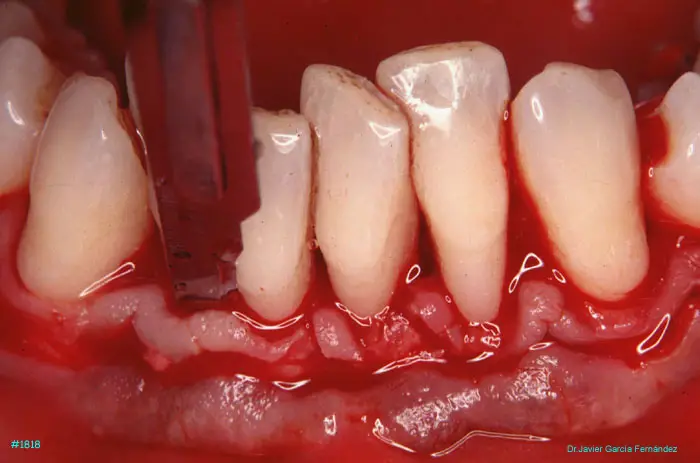

Atlas of Surgical Techniques in Periodontics. CASOS CLINICOS.

Atlas de Técnicas Quirúrgicas en Periodoncia